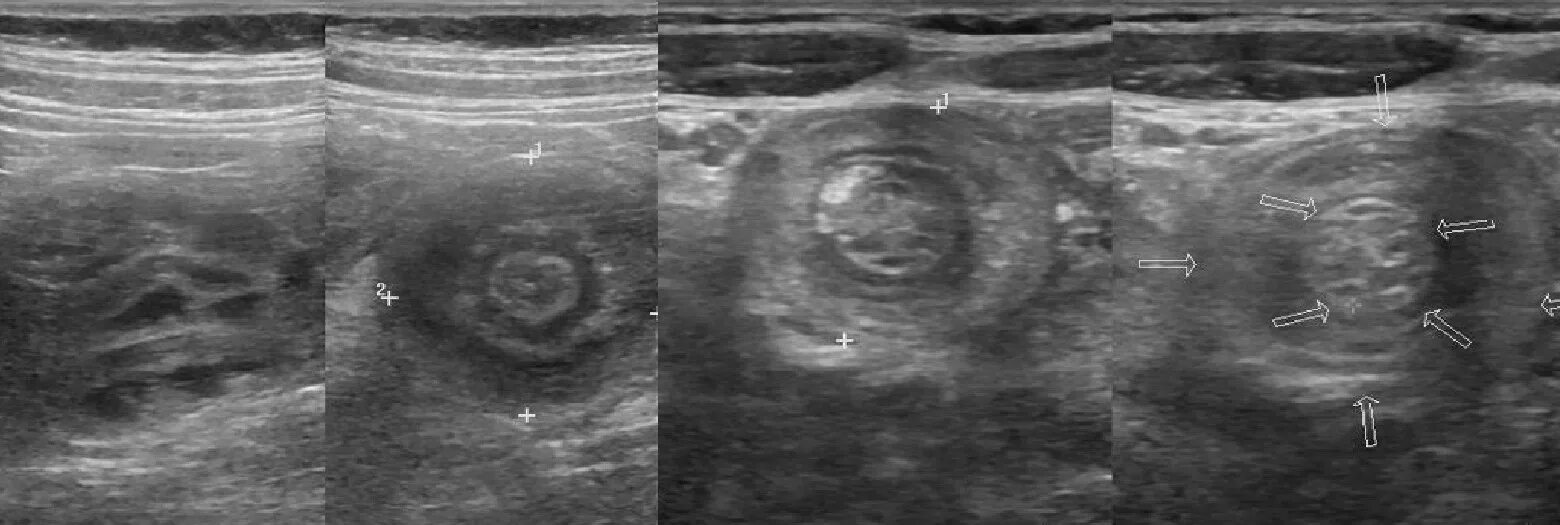

Непроходимость кишечника при онкологии